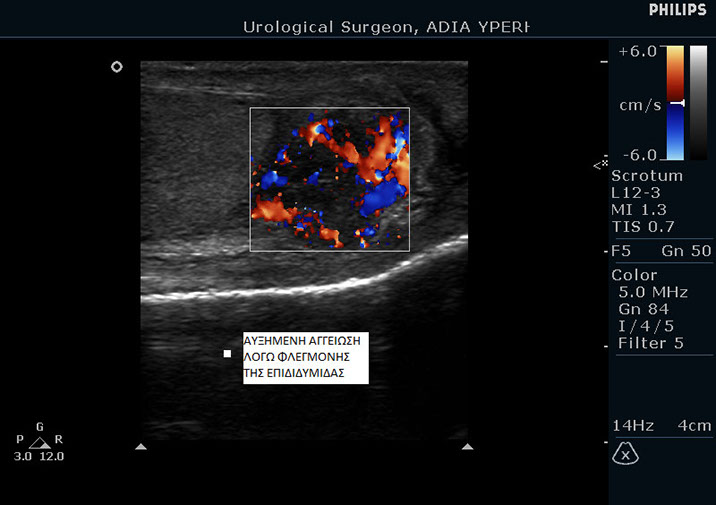

Επιδιδυμίτιδα του όρχι

Ως επιδιδυμίτιδα ορίζεται η φλεγμονή της επιδιδυμίδας σε κάποιον από τους δύο όρχεις. Επιδιδυμίτιδα ονομάζονται τα σωληνάκια που ξεκινάνε από τους όρχεις και μεταφέρουν το σπέρμα στην οπίσθια ουρήθρα.

Τα συμπτώματα της επιδιδυμίτιδας είναι πόνος έντονος στον όρχι, πρήξιμο, κοκκίνισμα του δέρματος και πυρετός, όποιος μπορεί να φτάνει τους 39 βαθμούς Κελσίου.

Η διάγνωση γίνεται εύκολα από τον ουρολόγο με τη βοήθεια υπερήχων και της κλινικής εξέτασης.

Η αντιμετώπιση της επιδιδυμίτιδας συνίσταται στη λήψη αντιβίωσης και αντιφλεγμονωδών φαρμάκων.